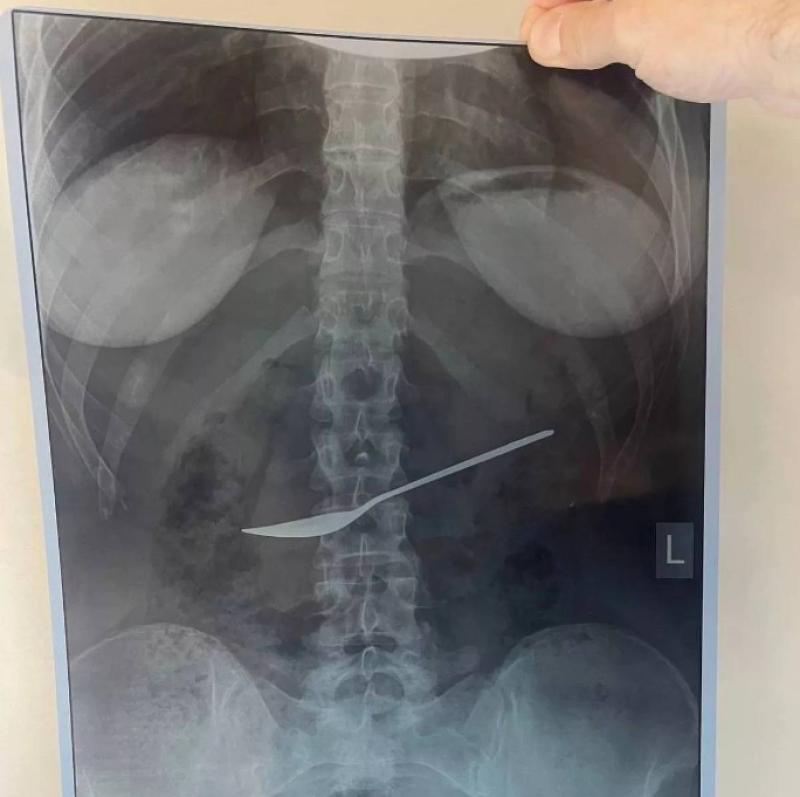

เข้าไปได้ไง! เด็กบ่นปวดท้อง หมอเอ็กซเรย์ช็อก เจอช้อนในช่องท้อง

จาก สื่อต่างประเทศ ได้รายงานว่า เมื่อวันที่ 7 พฤษภาคม ที่ผ่านมา แพทย์จากโรงพยาบาล Vologda State Regional Clinical Hospital ในประเทศรัสเซีย ทำการรักษาเด็กหญิงคนหนึ่งที่ร้องบ่นเรื่องปวดท้องอยู่ซ้ำๆ อย่างไม่ทราบสาเหตุ หลังจากทำการเอ็กซเรย์หลายครั้งเพื่อพยายามค้นหาสาเหตุของความเจ็บปวด ในที่สุดก็ค้นพบว่าสิ่งแปลกปลอมในท้องคือ ช้อนโลหะ ขนาด 8 นิ้ว (20 ซม.)

ทีมแพทย์กล่าวว่า เมื่อถูกส่งเข้ารับการรักษาในโรงพยาบาล เด็กหญิงก็เข้ารับการตรวจกระเพาะอาหารโดยใช้กล้องเอนโดสโคป ซึ่งช่วยให้แพทย์ยืนยันการวินิจฉัยได้ พวกเขาต่างตกตะลึงมากที่ภาพเผยให้เห็นชัดเจนว่ามีวัตถุโลหะยาว 8 นิ้ว ติดอยู่ในท้องของเธอ ซึ่งคาดว่ากลืนลงไปขณะรับประทานอาหารกลางวัน

สุดท้ายแพทย์ก็ดำเนินการตามขั้นตอนเพื่อช่วยนำสิ่งแปลกปลอมชิ้นนี้ออกจากกระเพาะอาหาร ผ่านการส่องกล้องทางหลอดอาหาร และเนื่องจากเด็กหญิงมีสุขภาพแข็งแรงดี จึงได้รับการปล่อยตัวกลับบ้านทันทีหลังจากทำหัตถการ พร้อมเตือนทุกคนงาม ดูแลตัวเองและจัดการสิ่งของต่าง ๆ อย่างระมัดระวัง